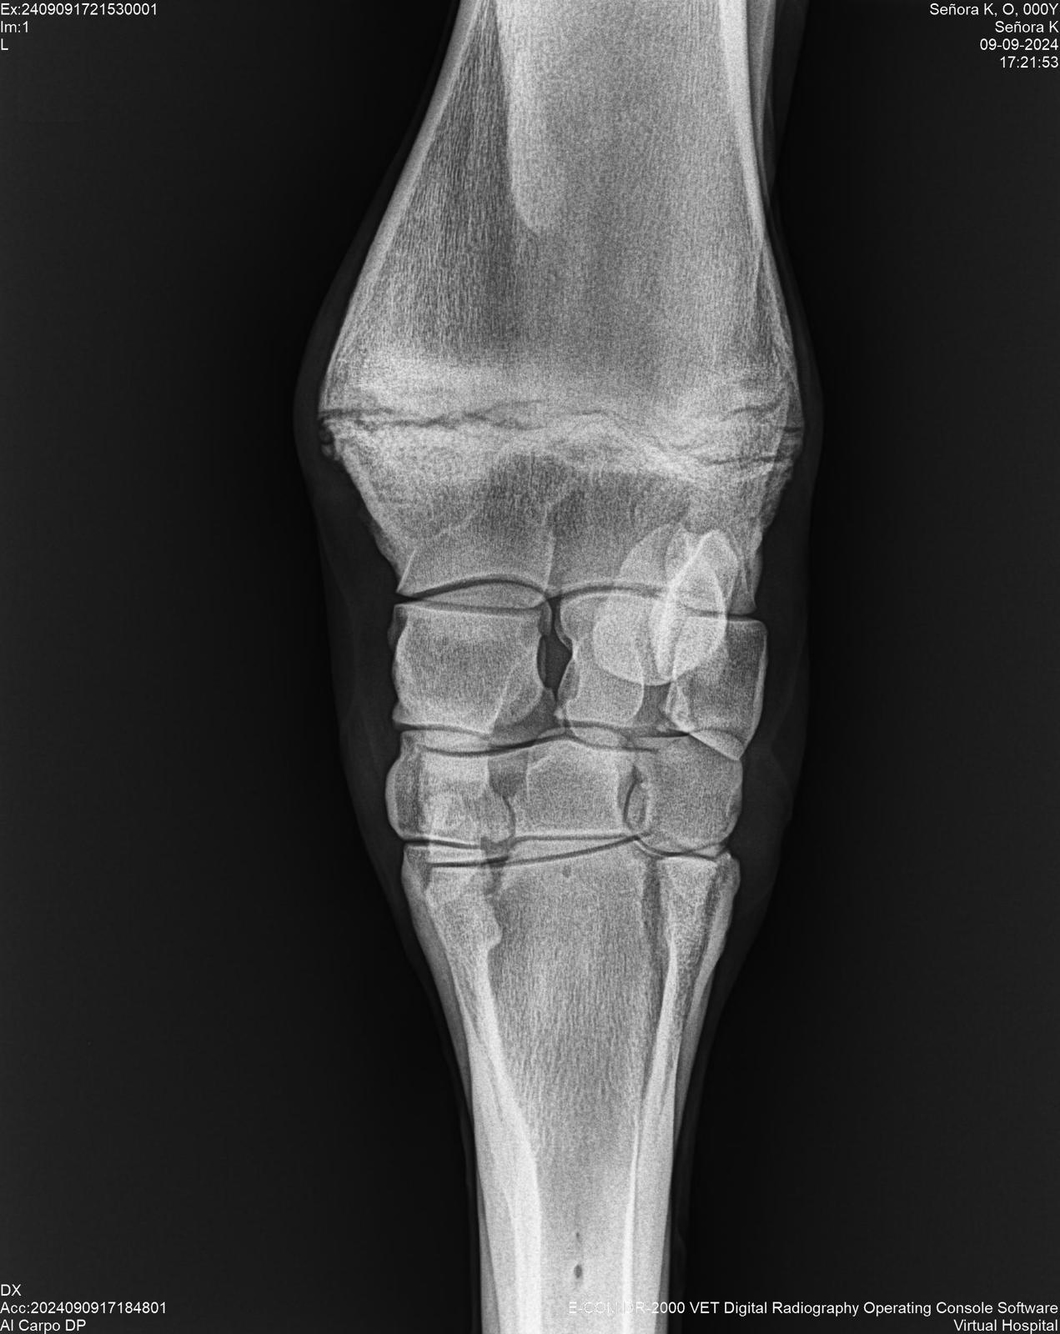

LOTE 44, SEÑORA K

Identificador: #291147-

Generacion 2022